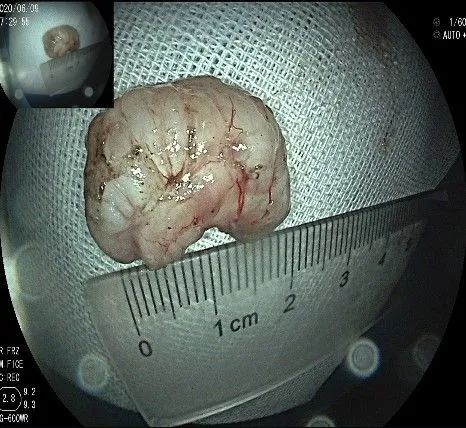

瘤子完整切除,随透明帽吸出的时候脱落到左侧会厌部,当时我们团队的麻醉、护理等人员都捏了一把汗,因为是静脉全麻没有插管,离声门太近了,一不小心进入气道会形成气管异物,造成严重后果!迅速换用鳄齿钳钳夹牢固,顺利取出!

完整的瘤体,呈不规则形状,长约2.0cm,宽度约0.8cm,有一定厚度,触之韧,像一颗白色的肾,表面有血管网。尽快浸泡送检。

术后暂禁食水,给予抑酸、抗感染、营养支持治疗,术后随访病人,诉术前的上腹疼症状消失,反酸、烧心症状减轻,其它无特殊不适,3天后病理结果回示,考虑:(贲门部)平滑肌瘤,建议其做免疫组化进一步鉴别间质瘤。